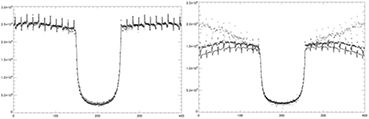

From figure 4, one can observe a noisier 202 keV sinogram when compared to the 307 keV sinogram. A study was performed to see if the transmission data was contaminated by the emission data and if the contamination is a function of emission source activity. 3 uniform phantoms (20 cm diameter × 26 cm in height) with varying activity from no activity to 0.5 mCi and 2.2 mCi were placed in the geometric center of the PET field of view. These phantoms were measured for 1 h and rebinned into the 2 transmission trues sinograms (prompts – delays). A profile across all the sinogram elements with summing over 100 angles and summing of all axial planes are shown in figure 5 for 202 and 307 keV transmission sinograms.

Figure 5. Profiles of the 307 keV (left) and the 202 keV sinograms. Profile is across all elements and sum of 100 angles and sum of all axial planes. No activity (-), 0.5 mCi (*) and 2.2 mCi (◊).

Standard image High-resolution imageThere is some contamination in the 307 keV transmission data around the edge of the object which can be seen as a small mismatch between the profiles. The 202 keV transmission data has more visible contamination from emission data. The tails of the sinogram increases in events further away from the center of the field of view. This may be a result of when the backscattering angle approaches 90° and the energies are close to equal to each other and both events fall into the 202 keV window. The change of the profiles in the region outside the objects boundaries in the cold phantom when compared to the region outside the object in the 307 keV profiles could be a result of the 307 keV photons scattering in the object into the 202 keV energy window.

A thought to make the 202 keV data usable is to model the 511 keV backscatter events and correct for these events in the collected data or add information to the 202 keV blank collection sinogram. This would recover the events that are discarded when emission activity is present in the scanner's field of view. It also creates a new transmission type flux that adds to the Lu-176 flux that's presented here. The model would require some information on the emission flux and the emission volume's attenuation information. Both of these pieces of information are available from the current technique using only the 307 keV transmission data. Since it was shown that the 307 keV transmission data is mostly uncontaminated by emission data, the attenuation maps produced from this data can be used for the initial emission reconstruction. Using the emission distribution, a model of the backscattering of 511 keV photons can be performed to correct for the increase of counts not accounted for in the blank scan. This would allow for the removal of the condition where if the first event is in the 202 keV energy window, the second event cannot be in the 307 keV window. Figure 12 illustrates the additional information that can be acquired by not applying the backscatter condition to the 202 keV transmission data. The figure is a re-plot of figure 5 with 2.2 uCi and a cold 20 cm uniform phantom in the center of the field of view. It is seen that the addition of the backscattered events almost doubles the amount of events in the 202 keV transmission data. This increase of information is dependent on the amount of activity that illuminates the detectors.

Figure 12. Profile of 202 keV sinograms plotted the same as figure 5. The sinograms of the cold phantom (–) and the 2.2 mCi phantom (◊) were acquired and rebinned without the discrimination of backscattered events.